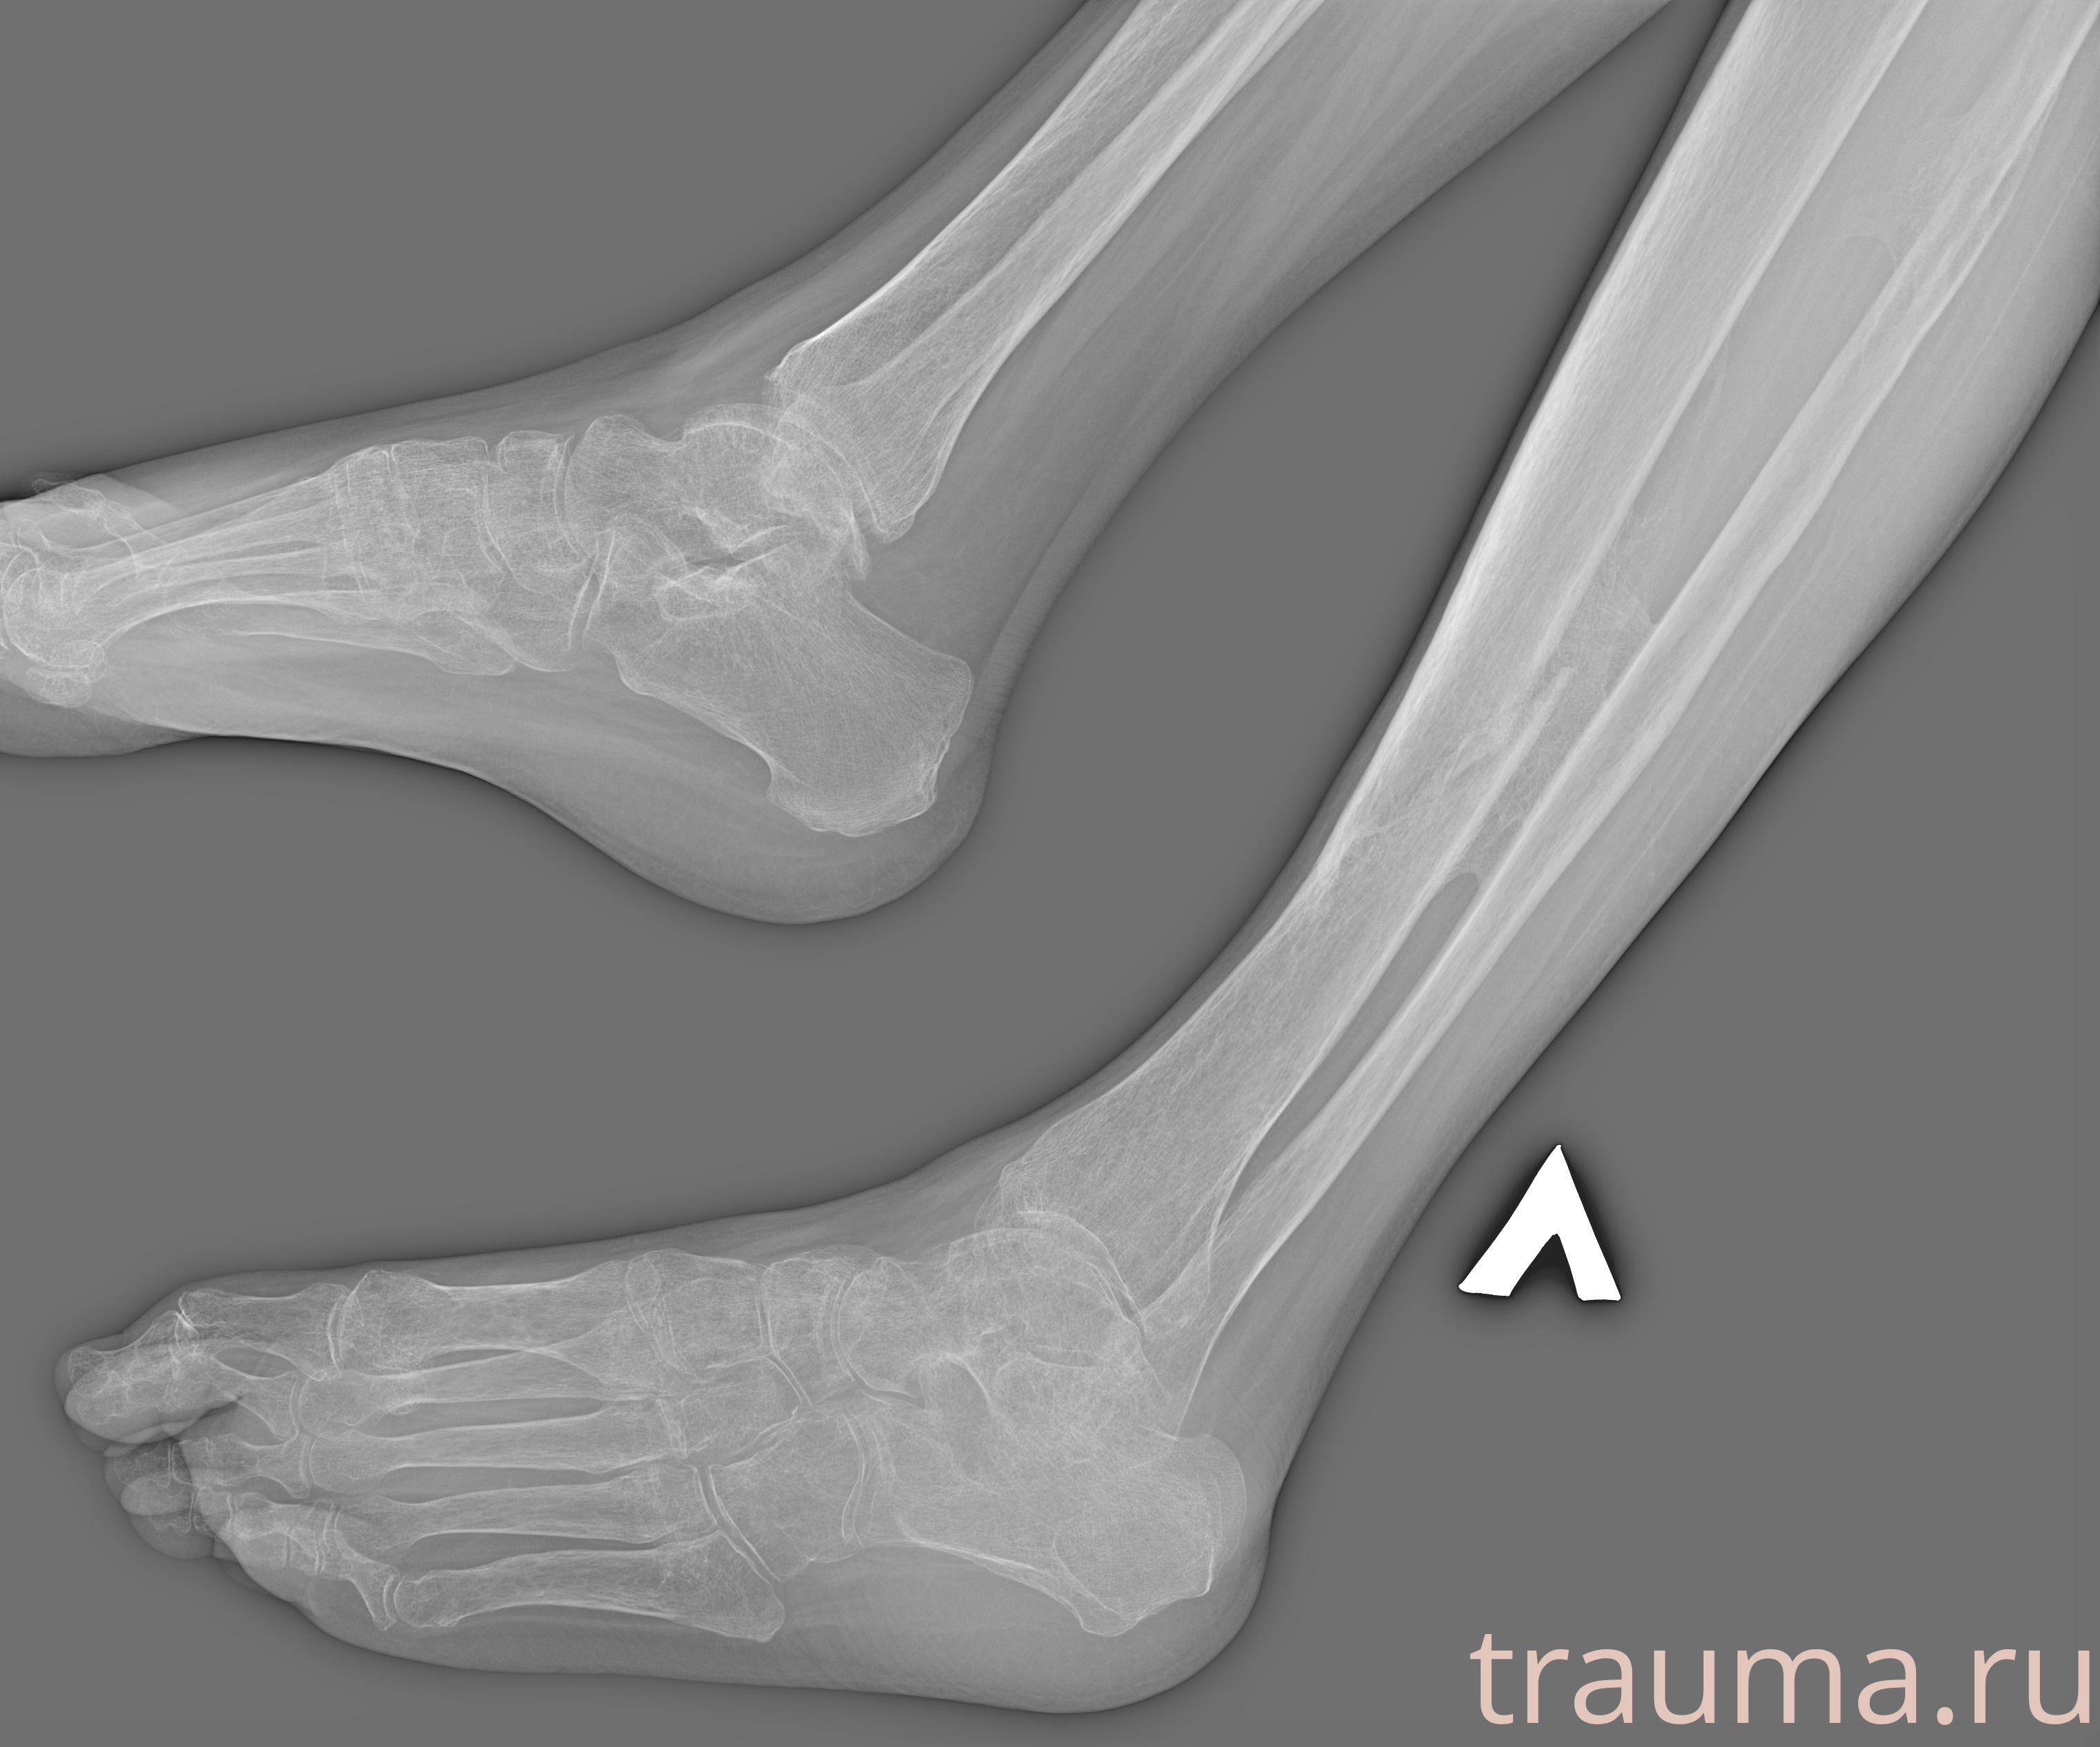

Рентген на дому: по вашему адресу приезжает врач-рентгенолог, травматолог-ортопед с мобильным рентгеновским аппаратом, проводит диагностику травмы или заболевания, делает необходимые рентгенограммы, дает рекомендации по дальнейшему лечению. Получить качественные снимки в домашних условиях возможно благодаря уникальной методике, разработанной МосРентген Центром для института  Склифосовского